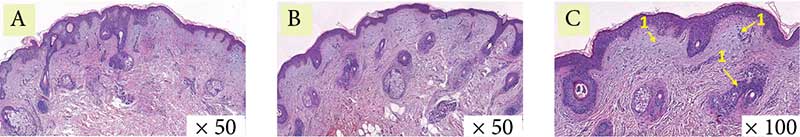

Рис. 8. Пациентка 3. Окраска по Ван-Гизону: A – до процедуры, B и C – через месяц после процедуры (стрелка указывает на участок упорядочения и структуризации коллагеновых волокон)

Рис. 9. Пациентка 3. Окраска по Массону: A – до процедуры, B и C – через месяц после процедуры (стрелка указывает на участок упорядочения и структуризации коллагеновых волокон)

Гистологическая картина демонстрирует уменьшение гиперкератоза, сглаживание эпидермальных гребней. В сосочковом слое дермы отмечаются компактизация и реорганизация коллагеновых волокон, в сетчатом слое дермы коллагеновые волокна стали более структурированными и упорядоченными (рис. 7–9).